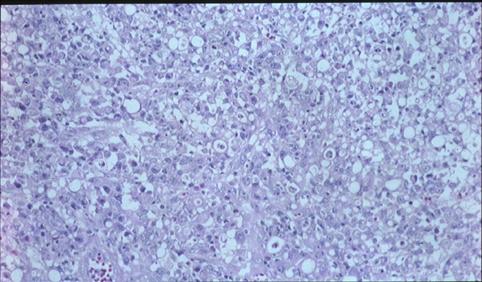

以隆起为主体的5型胃印戒细胞癌的病理组织照片(微观)   切除胃的肿瘤部分的HE染色的增强扩大照片。在这个部分可见有缺乏胞体的低分化癌和印戒细胞癌(signet ring cell carcinoma)混合存在。

疾病(病理主体)的分类恶性上皮性肿瘤/印戒细胞癌

检查方法病理切片(微观)

肿瘤的肉眼分类5型(难以分类)/

肿瘤最大直径40以上

肿瘤的深度mp